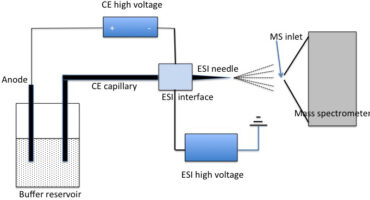

31 March 2023 by admin, in TechnologyCAPILLARY ELECTROPHORESIS (CE)

Akin to HPLC, electrophoresis is another emerging technology chaperoning the dia...READ MORE + 31 March 2023 by admin, in Technology